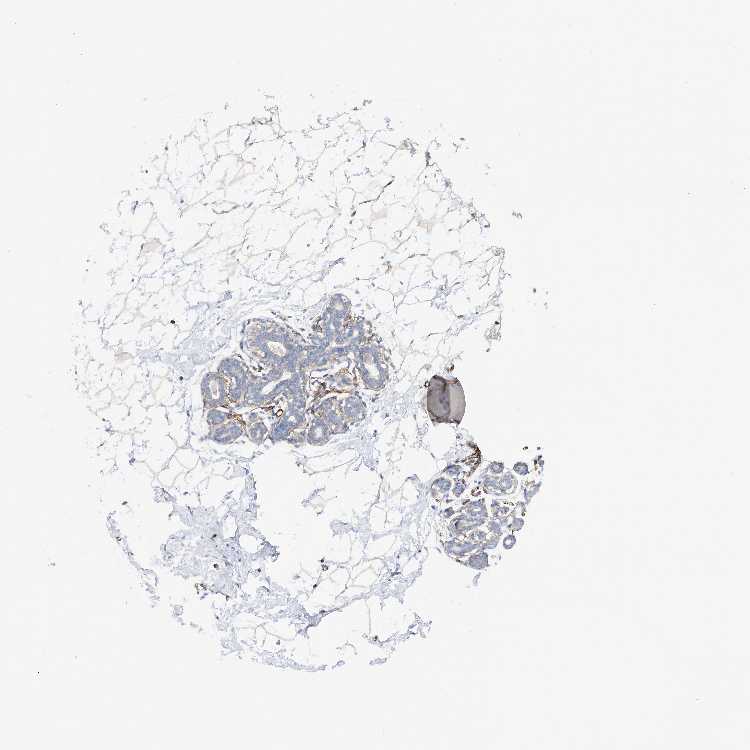

BREAST - Antibody stainingi

Antibody staining in the annotated cell types in the current human tissue is reported as not detected, low, medium, or high, based on conventional immunohistochemistry profiling in selected tissues. This score is based on the combination of the staining intensity and fraction of stained cells.

Each image is clickable and will lead to virtual microscopy that enables deeper exploration of all samples and also displays staining intensity scores, fraction scores and subcellular localization as well as patient and tissue information for each sample.

Antibody HPA029053Antibody HPA029055

Adipocytes Not detectedLow

Glandular cells Not detectedMedium

Myoepithelial cells LowMedium